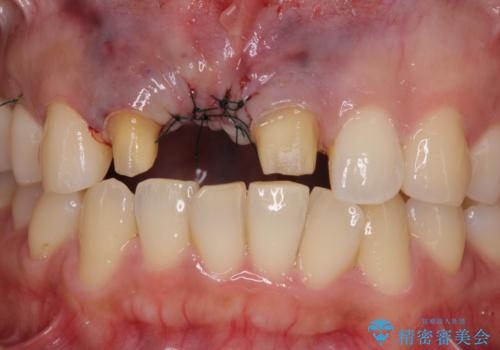

抜歯後は歯肉が痩せてしまうため、歯肉移植を行って歯肉の形態を改善した後、オールセラミックブリッジにて補綴することとしました。

歯肉移植により歯肉ラインや歯の形態を整えることができ、ブリッジによる補綴としたことで舞えば全体の色調を整えることができました。

- 外科手術のため、術後に痛みや腫れ、違和感を伴います

- 歯周組織再生治療は患者様の状態によって術後の経過が異なります(見た目が改善しない場合もあります)